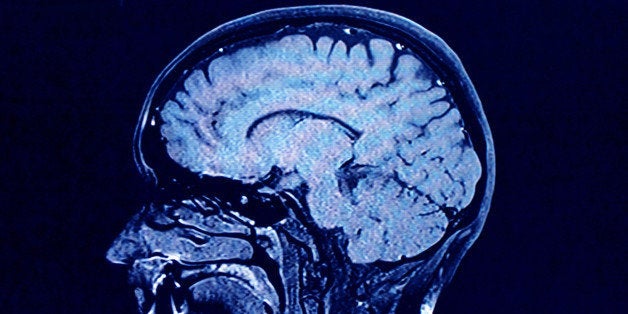

Stress is affecting your brain much more than you think. Sure, you've experienced the distraction, forgetfulness, negativity or anxiety that comes from stressful situations, but did you know it's also shrinking your brain? Hormones released in response to stress not only affect brain function, they also change the physical structure of your brain.

The stress hormone cortisol can kill, shrink, and stop the generation of new neurons in a portion of the brain called the hippocampus. (1) The hippocampus is critical for learning, memory and emotional regulation, as well as shutting off the stress response after a stressful event is over: all much-needed processes in both our professional and personal lives.

Chronic stress can also shrink the medial prefrontal cortex. (2) This negatively affects decision making, working memory, and control of impulsive behavior. Stress also has the ability to affect stem cells, inhibiting access to the prefrontal cortex, where we plan complex cognitive behavior and moderate social interaction. The result is a brain that is less capable of learning and memory, and more prone to anxiety and depression.

To make matters worse, these same stress hormones can increase the size and activity of a portion of the brain called the amygdala. (3) The amygdala is critical in the formation and storage of memories associated with highly emotional events. It pairs an event with a feeling, and this connection is stored away in our long-term memory so we can either avoid the event or seek it out in the future. The changes cortisol creates increase negative emotions such as fear, anxiety, and aggression.